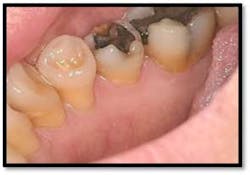

Treatment: FM Perioscopy completed in two, 2-hour sessions with local anesthetic and micro ultrasonics. No hand instruments are necessary during Perioscopy.

Note: When instrumenting “blindly,” the end point is unknown and debris is left behind. Visualization via the Perioscopy System ensures effective treatment is rendered because the bioburden is completely removed. Ultrasonic instrumentation is not only effective and efficient for thorough bacterial removal, but is an easier therapy to tolerate for the patient, with less sensitivity post treatment.9 months Post Treatment:

Charting shows that all pockets are now generalized 1-3 mm with no BOP